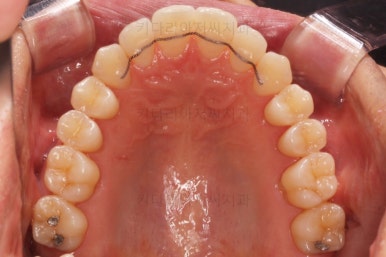

장치를 처음 부착했을 때의 입안 모습입니다.

아랫니가 해야될 작업이 많고 기간이 오래 걸리기 때문에 윗니는 최대한 늦게 장치를 부착하여 불편감을 최소화 하기로 했어요.

이번에 사용한 장치는 자가결찰 세라믹장치입니다. Empower clear(엠파워 클리어)라는 장치이고 흔히 많이들 알고계신 클리피씨와 동일한 유형의 장치에요.

클리피씨, 엠파워 등은 제품 이름일 뿐이죠. 클리피씨는 일본회사 장치, 엠파워는 미국회사 장치에요. 부산비수술교정 키다리아저씨치관느 여러 가지 이유로 엠파워 장치를 클리피씨보다 더 선호해요.

이 뽑은 자리로 앞니를 쭈욱 밀어넣으며 비대칭도 맞춰주기 위해서 미니스크류(마이크로 임플란트)라고 불리는 작은 나사를 잇몸뼈에 식립했어요.

이를 지지대로 삼아서 치아를 움직이게 됩니다.